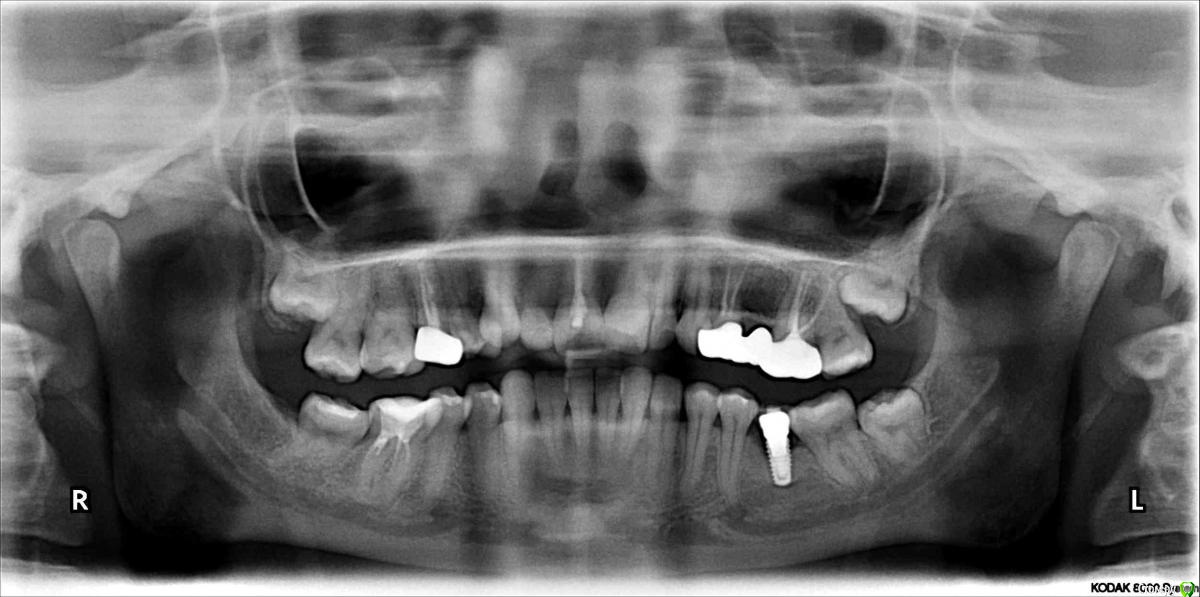

Нина86 Опубликовано 14 августа, 2019 Поделиться Опубликовано 14 августа, 2019 Здравствуйте! Проконсультируйте, пожалуйста, по поломке импланта. 5 лет назад поставила зубной имплант фирмы Megagen (диаметр 4 мм, длина 8,5 мм, Южная Корея, там и ставила).Месяц назад он сломался (сам имплант). На вопрос: "Почему же так произошло?" два стоматолога сказали, что не знают, просто импланты иногда (редко) ломаются. При внимательном рассмотрении панорамных снимков у нас с мужем возник вопрос, а не мог ли имплант сломаться из-за зачатка зуба мудрости, который давил на соседний зуб, а он, в свою очередь, на коронку импланта? Если это могло быть так, то нужно ли удалять зачаток зуба мудрости с той стороны, где имплант, перед установкой нового импланта или это можно сделать после его установки? И последний вопрос: можно ли устанавливать новый имплант в один день с удалением сломанного импланта? Снимки за 2017, март 2019 (до поломки импланта) и за июль 2019 (после поломки импланта) приведены ниже. Огромное спасибо! Ссылка на комментарий

колесников Опубликовано 15 августа, 2019 Поделиться Опубликовано 15 августа, 2019 Почему сломался? Можно только предполагать,но вероятно тут несколько предпосылок к этому было.Во первых ,как видно на снимке,стенка импланта довольно тонкая. Хотя диаметр 4.0 пригоден для установки в области моляров,в данном случае нагрузка оказалось запредельна для стенки такой толщины и для этого сплава . Во вторых ,почему сломался,ведь там внутренний конус? Да на коническом соединении мы получаем минимальную нагрузку на внутреннюю стенку шейки импланта и проблема перелома должна нас не волновать. Но! На корейских системах не оригинальный конус морзе,другой градус,вероятно градус имеет значение.В третьих,так же по снимку можно предположить ,что абатмент платформой «не сел» ,возможно не оригинальный,не правильное распределение нагрузки,как итог микролюфт и переломВ четвёртых,перед фиксацией коронки заметно что имплант более 1/3не в кости. Перелом проходит по костной границе . Вероятно были избыточные боковые нагрузки что привело к микролюфту и перелом произошёл по границе интегрированного с неинтегрированым. Ссылка на комментарий